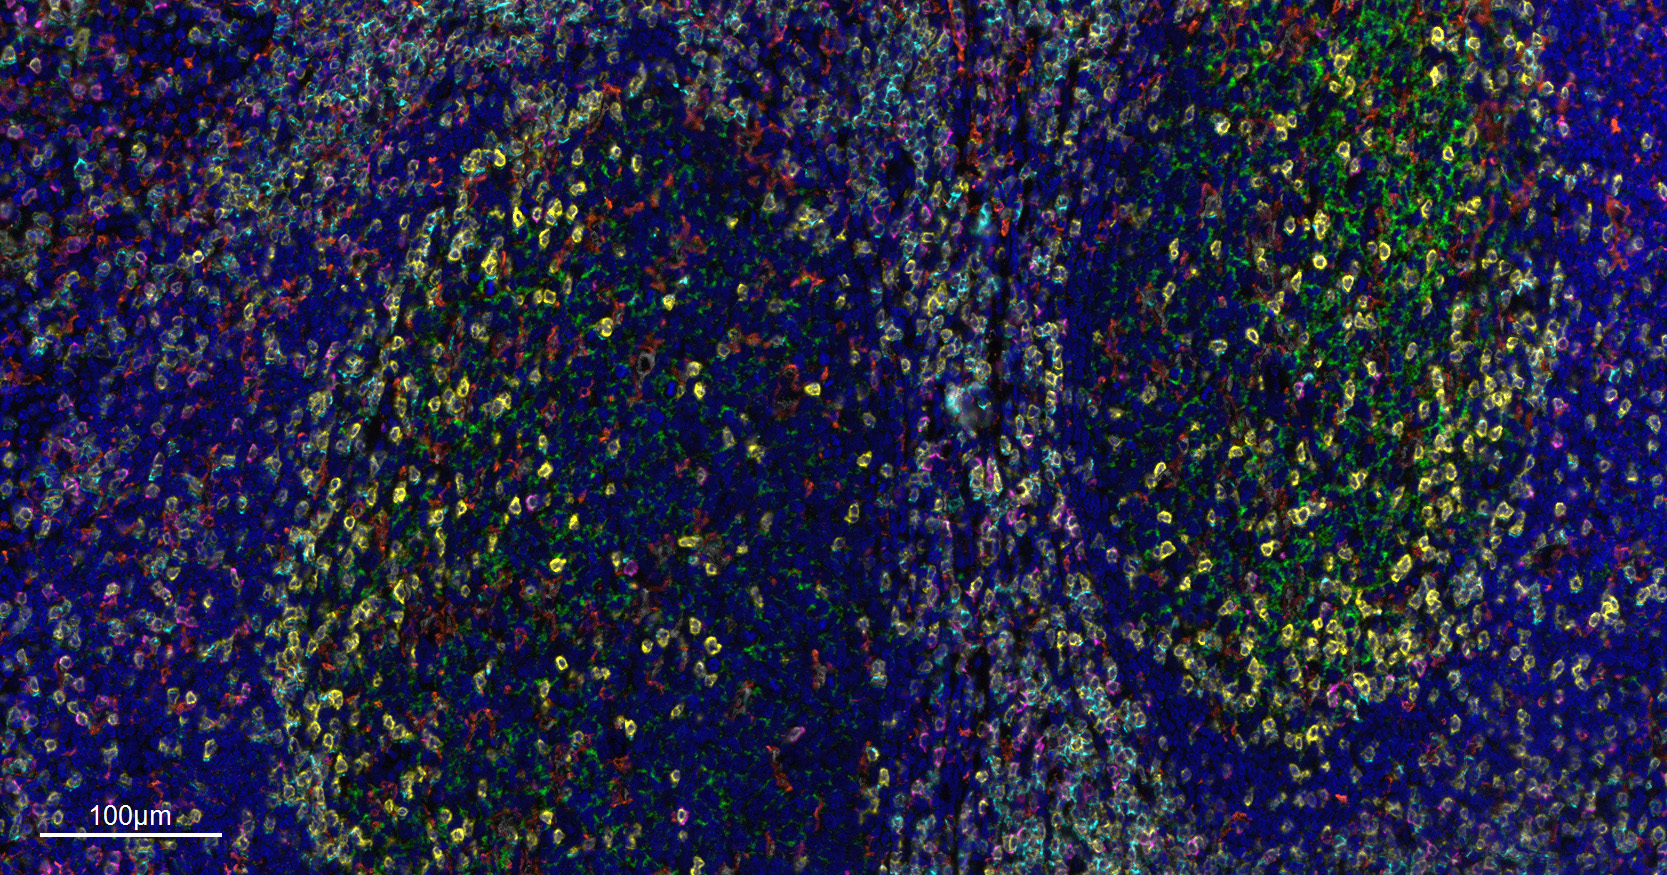

CD68 Recombinant Antibody

Applications IHC-P, IHC-F, IF(ICC), IF, Flow-Cyt